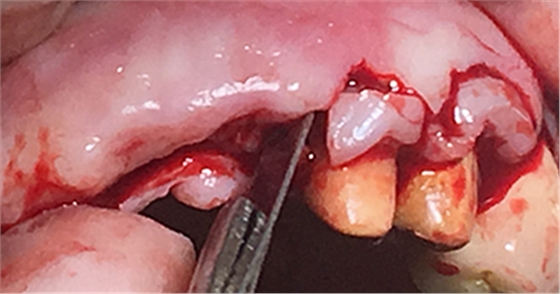

設計:1.僅做牙槽嵴頂水平切口,不做垂直切口,2.缺牙區(qū)由三顆牙改成兩顆牙,3.鄰牙冠延長。

水平切口,鄰牙冠延長。

擴孔,檢查方向。